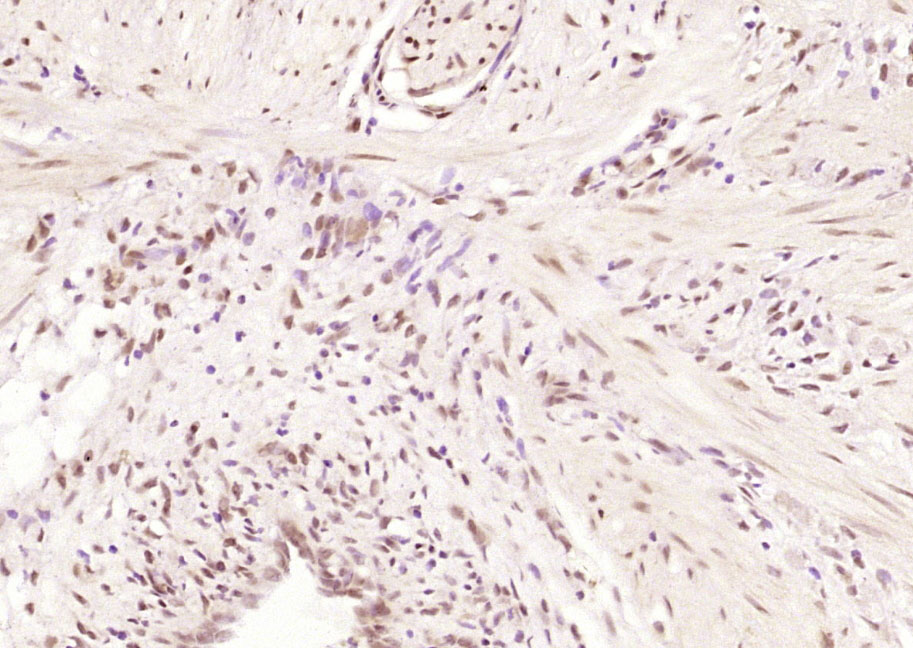

| 英文名称 | GEM Rabbit pAb |

| 中文名称 | GTP结合丝裂原诱导T细胞蛋白抗体 |

| 产品应用 | IHC-P=1:100-500, IHC-F=1:100-500, IF=1:100-500 Not yet tested in other applications. |

| {IHC-P} | {1:100-500} |